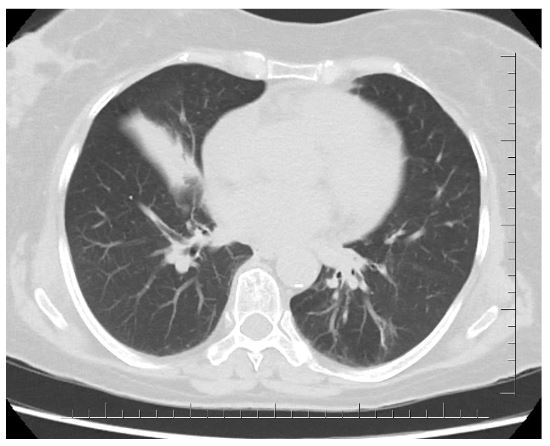

Chest CT-scan suggested middle lobe atelectasis (Figure 2). QuantiFERON-TB Gold test was positive.